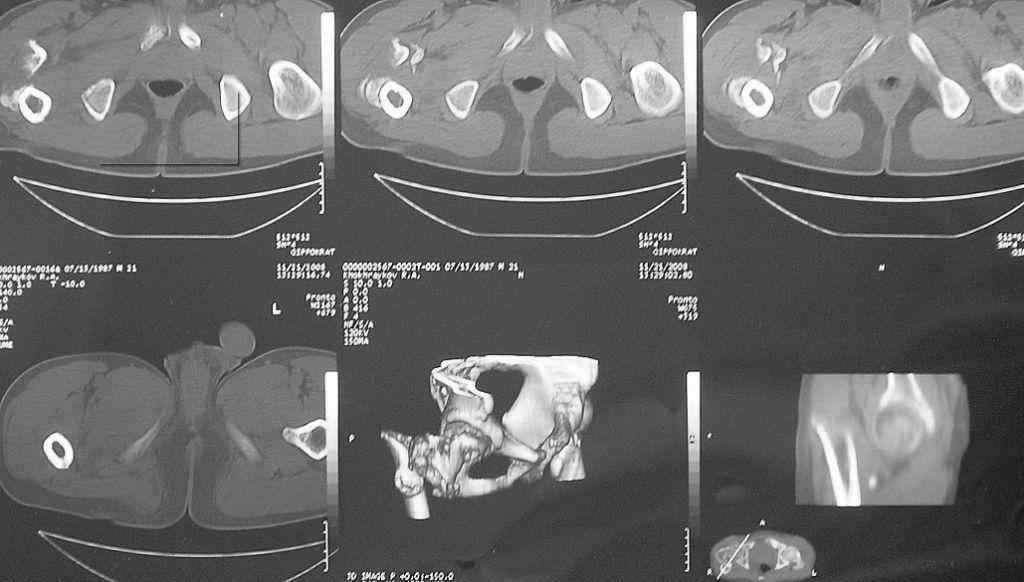

Уважаемые коллеги! Нужен совет. Больной Х., 21 год, ДЗ: ложный сустав вертельной области

правого бедра. Травма 8 мес. назад, ДТП, получил закрытый межвертельный перелом правого

бедра. Лечился в городской больнице одного из городов-спутников г. Караганды скелетным

вытяжением в течение 3 недель, затем кокситной гипсовой повязкой 2 мес.

В настоящее время имеется укорочение конечности на 7 см, умеренная

боль в вертельной области; ходит без костылей, полностью нагружая

больную конечность, при нагрузке отмечается смещение дистального

отломка проксимально примерно на 1,0 см.; объем движений в коленном

суставе сохранен; при пальпации отломков боли нет, умеренная

патологическая подвижность.